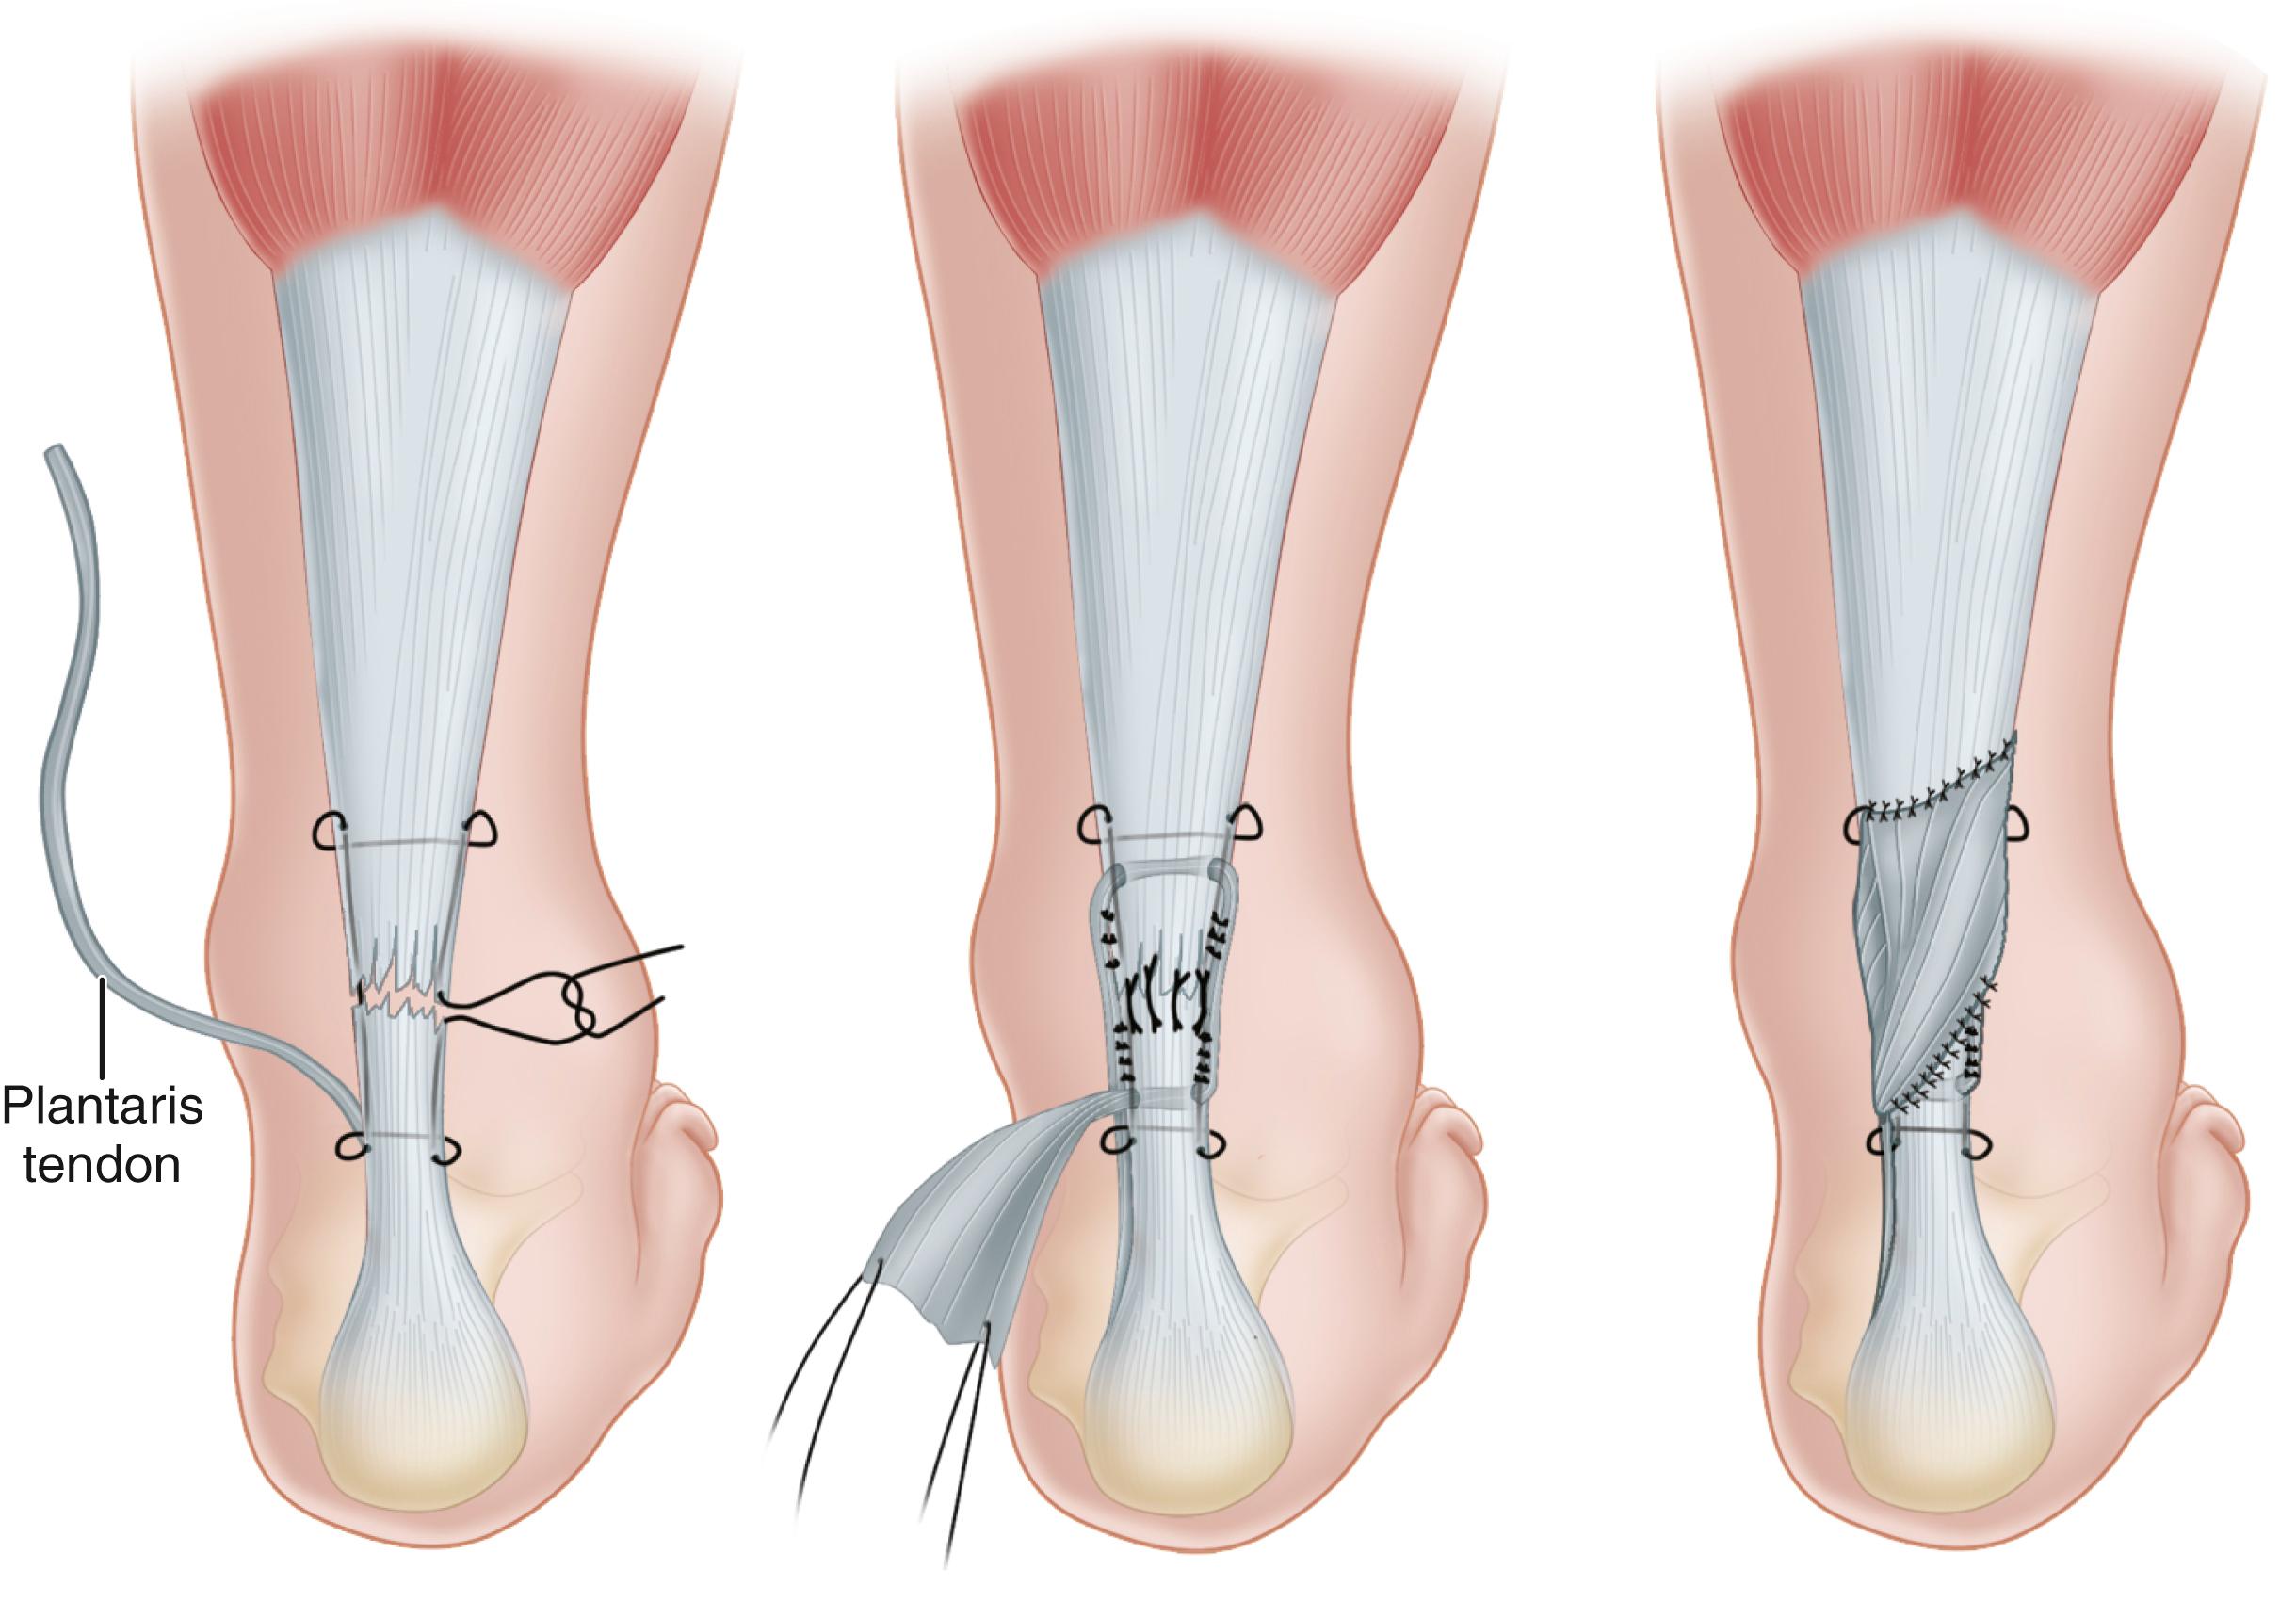

• If the plantaris tendon is intact ( Fig. 48.18A ), divide its insertion on the calcaneus; then, using forceps and beginning distally, fan out the tendon to form a membrane.

FIGURE 48.18, Lynn technique for repairing fresh rupture of Achilles tendon. A, Ruptured Achilles tendon has been sutured, and plantaris tendon has been divided distally and is being fanned out to form membrane. B, Fanned-out plantaris tendon has been placed over repair of Achilles tendon and sutured in place. SEE TECHNIQUES 48.10 AND 48.16.

• Place this membrane over the repair of the Achilles tendon and suture it in place with interrupted sutures ( Fig. 48.18B ). When possible, cover the Achilles tendon for 2.5 cm both proximal and distal to the repair.

• If the plantaris tendon also is ruptured, dissect it free from the Achilles tendon for several centimeters and divide it proximally, using a tendon stripper.

• Then pull the tendon distally into the incision, fan it out as a free graft, and cover the repair as already described.

• Close the sheath of the Achilles tendon as far distally as possible without tension and close the wound.